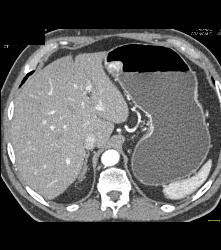

Glomus Tumor